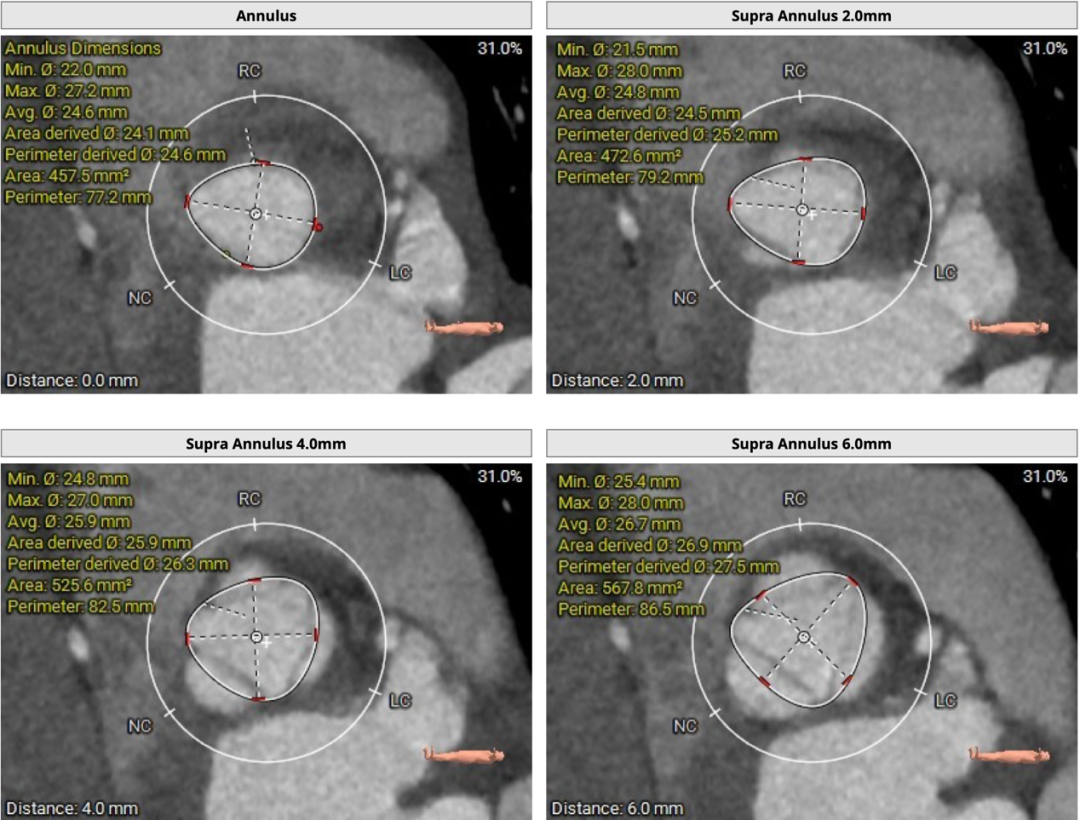

患者主动脉瓣三叶式,瓣叶基本等大,瓣叶不厚,瓣叶未见明显钙化。主动脉瓣环周长折算直径约24.6mm:

左侧冠脉开口高度低,LCA 9.8mm,左冠瓣瓣叶长度约12.8mm;右侧冠脉开口高度可,RCA 14.3mm:

术中建议造影角度RAO 7°,CAU 14°(其它参考角度如下图):